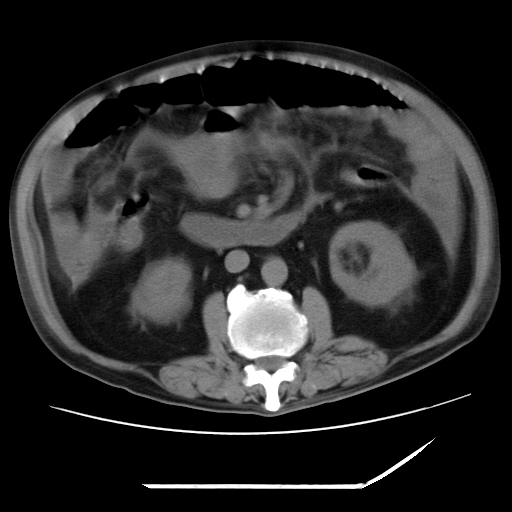

以下是引用zxl51642在2009-8-12 18:55:00的发言:[br]1、肠系膜脂肪浑浊,密度增高,腹水,支持腹膜炎诊断;2、右肾盂及输尿管中段结石,左输尿管起始段结石;3、胆囊切除术后改变?4、双侧胸膜腔少量积液;5、胰腺体积不大,勾勒清楚,肾前筋膜无增厚,不支持胰腺炎,请结合血尿淀粉酶及临床。